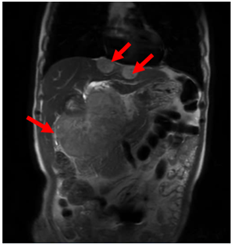

UNG THƯ BIỂU MÔ TẾ BÀO THẬN

Ung thư thận là loại ung thư thường gặp đứng thứ 14 trên toàn cầu, với hơn 430.000 ca mới được chẩn đoán vào năm 2020, và 434840 ca mắc trên toàn cầu vào năm 2022. Tỷ lệ mắc thay đổi theo khu vực địa lý, cao hơn ở châu Âu và Bắc Mỹ. Ung...